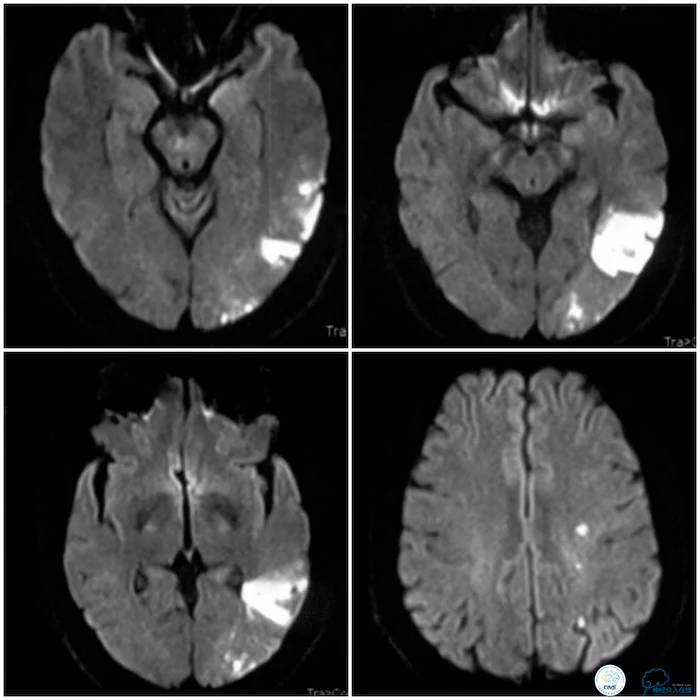

患者,男性,50岁,主因“右侧肢体无力伴言语不利2个月”入院。患者2个月前无明显诱因出现右侧肢体无力,表现为右上肢持物欠稳,右下肢行走拖曳,伴命名性失语,肢体无力持续约5分钟好转,但仍有言语笨拙。至当地医院就诊,查头颅MR示左侧颞枕分水岭区脑梗死(图1)。

图1

查头颅CT示左颞枕叶分水岭脑梗死(图2)。

图2